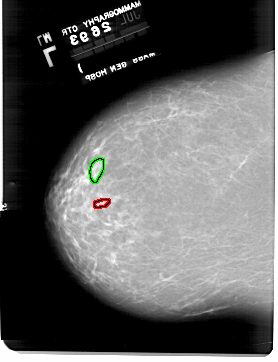

A_1918_1.LEFT_CC

LEFT_CC LINES 6511 PIXELS_PER_LINE 4996 BITS_PER_PIXEL 12 RESOLUTION 43.5 OVERLAY

FILE: A_1918_1.LEFT_CC.OVERLAY

TOTAL_ABNORMALITIES 1

ABNORMALITY 1

LESION_TYPE CALCIFICATION TYPE PLEOMORPHIC DISTRIBUTION CLUSTERED

ASSESSMENT 4

SUBTLETY 2

PATHOLOGY BENIGN

TOTAL_OUTLINES 1

BOUNDARY

ABNORMALITY 2